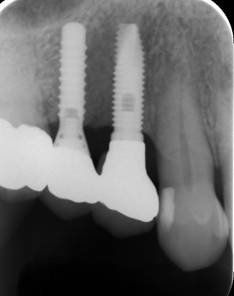

歯周病で抜歯せざるを得ず、インプラントを希望されたケース(使用インプラントはスプライン)

術前。すべての歯が歯周病の末期状態でブリッジ全体がうごいて噛めないとの訴え。右上の犬歯が腫れていました

固定式のブリッジが入っていましたが歯周病で動いています

治療後。歯周病で失われた骨が回復しています。使用インプラントはスプラインツイストです。

上部構造装着後6年。ハイブリッドレジンを使用したため、少し艶がなくなってきました。上部構造の材料には金属、ハイブリッドレジン、セラミックなどがあります。セラミックはきれいですが欠けやすいため、最近はフルジルコニアを使っています。

インプラント装着後6年。順調に経過しています。12か月毎のメインテナンスをしています。